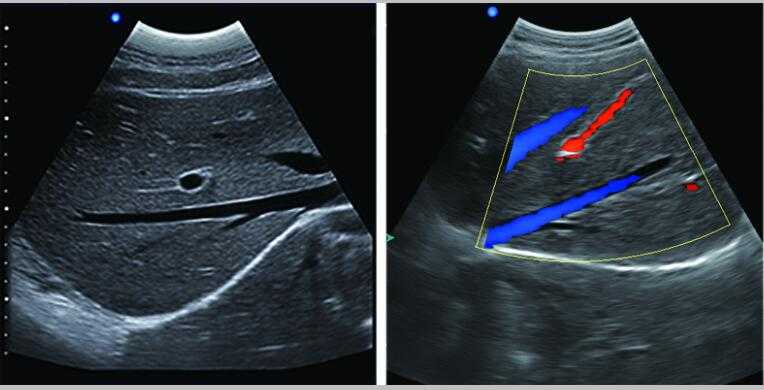

L3-VET便攜筆記本式獸用B超機適用探頭